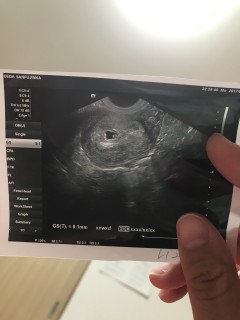

胎嚢がいびつで小さいから流産しちゃうかも...と言われ1週間ぶんのクスリをもらいました。 心拍は確認できなかったので不安ですが赤ちゃんを信じて来週の検診で成長しているのを祈っています。

まだ早すぎて赤ちゃんは見えなかったけど、子宮内でひとまず安心。これから何事もなく育って、元気に産まれてきますように。